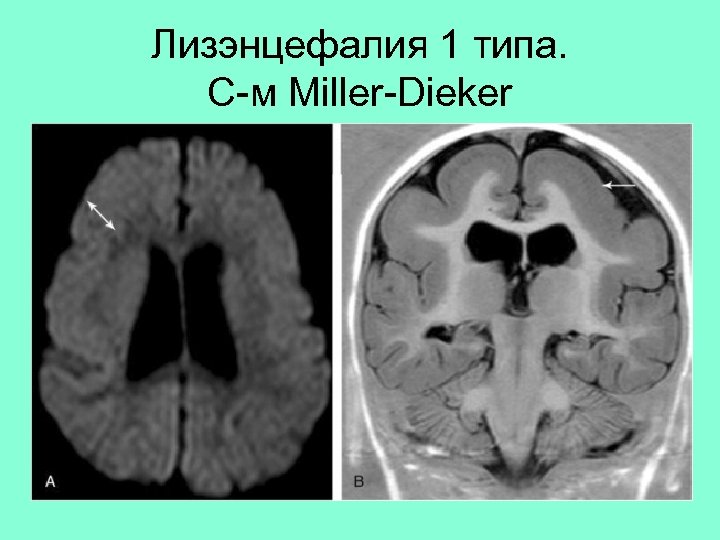

Лизэнцефалия 1 типа. С-м Miller-Dieker